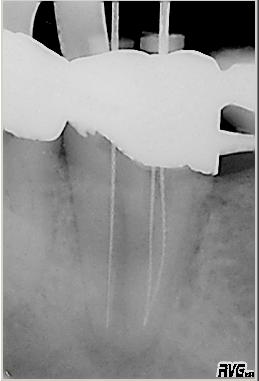

Erste Messaufnahme

Erste Messaufnahme nach Entfernung der Guttapercha. Es erfolgt ein vorsichtiges „Herantasten“ an die Resektionsstelle. Da die Endometrie in diesem Fall keine reproduzierbaren Ergebnisse anzeigt, erfolgt die erste Messaufnahme mit deutlichem „Sicherheitsabstand“ zur Resektionsstelle. Der Patient ist bereits nach der ersten Sitzung beschwerdefrei.